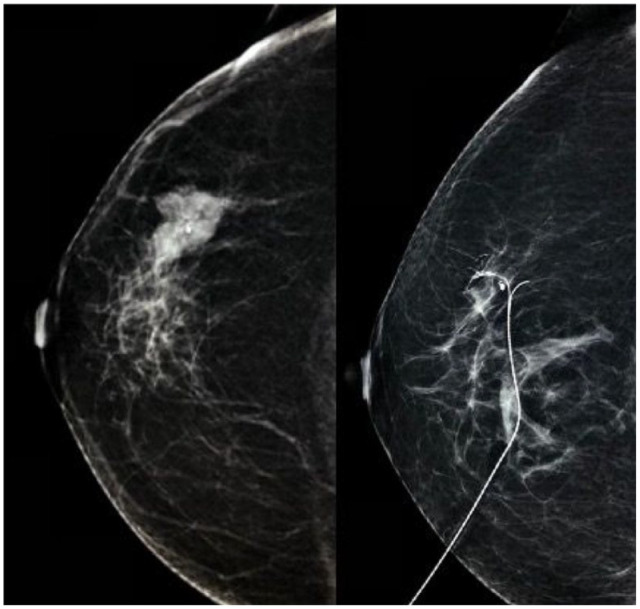

Methods: This was a prospective study conducted between October 1, 2019, and March 31, 2021. Patients with early breast cancer, estrogen and progesterone receptors negative and either Her2 positive or negative, and who were fit to undergo marker placement at the centre of the tumour and to receive third-generation chemotherapy (4 cycles of 3 weekly doxorubicin and cyclophosphamide followed by 4 cycles of 3 weekly docetaxel) were included in the study. Following the enrolment, a tissue marker was placed at the centre of the tumour and appropriate chemotherapy was started. Patients who achieved clinical complete response were subjected to ultrasound-guided vacuum-assisted biopsy (VAB) from the tumour bed before surgery. Pathology results of the VAB and resected specimen were then compared. Descriptive statistics were used in the study.

Results: Eighteen patients were enrolled in the study, with a mean age of 43.6 ± 9.8 years. However, only 10 were eligible for VAB procedure, and sensitivity and specificity were calculated based on the results of these 10 patients only. Vacuum-assisted biopsy showed sensitivity of 50% and specificity of 100% in identifying pCR. Combination of mammography, ultrasonography, and VAB showed sensitivity of 77.8% and specificity of 66.7% in identifying pCR.